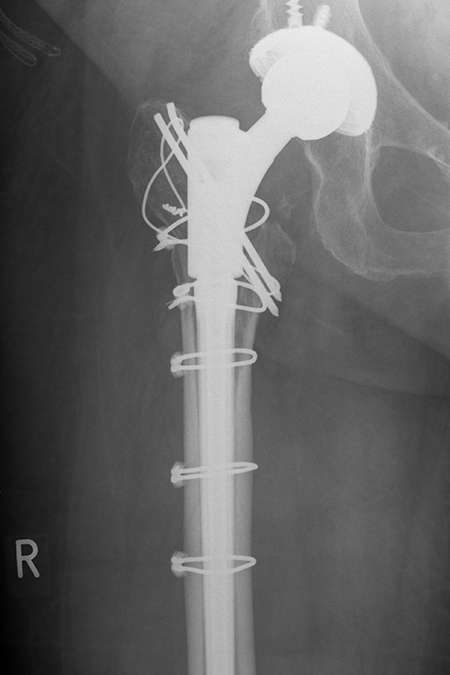

Neu eingesetzter längerer modularer Hüftschaft mit anatomischer Fixierung des Knochenbruches durch Drähte.

Ausgebrochener Prothesenschaft, der Knochen ist am unteren Ende nach außen abgespreizt (Vancouver B2).